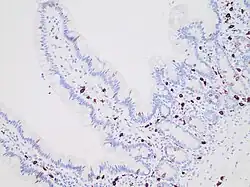

Systemic mastocytosis involves the bone marrow in the majority of cases and in some cases other internal organs, usually in addition to involving the skin. Mast cells collect in various tissues and can affect organs where mast cells do not normally inhabit such as the liver, spleen and lymph nodes, and organs which have normal populations but where numbers are increased. In the bowel, it may manifest as mastocytic enterocolitis.[15] However, normal ranges for mast cell counts in the gastrointestinal tract mucosa are not well established in the literature, and depend upon the exact location (e.g. right versus left colon), gender, and patient populations (such as asymptomatic patients versus patients with chronic diarrhea of unknown etiology). Quantitative mast cell stains may yield little diagnostic information, and further research studies are warranted to determine whether "mastocytic enterocolitis" truly represents a distinct entity.[16]